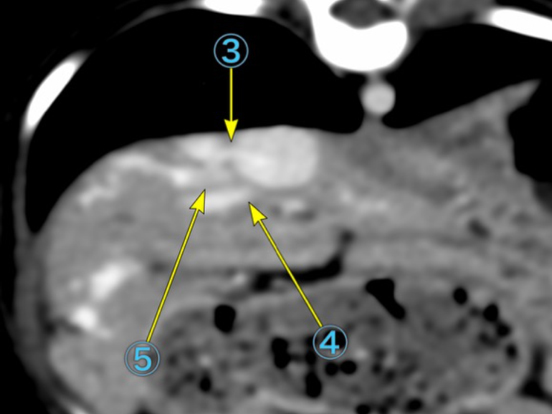

肝内門脈シャントの精査を目的にCT検査を実施しました。検査の結果、右外側肝葉において肝内門脈から体循環へのシャントが確認され、後大静脈へ流入する血管が約5本(うち1本は太く、残りの4本は細い)存在することが判明しました。 また、右外側肝葉への血流が非常に豊富である一方、他の肝葉への門脈血流は細いことが確認されました。そのため、右外側肝葉切除を行った場合には術後に門脈圧亢進を生じる可能性が高いと判断されました。 これらの所見を踏まえ、段階的な肝内門脈シャント閉鎖を目的とした血管プラグ塞栓術を希望され、施術する運びとなりました。

手術前のCT検査での評価